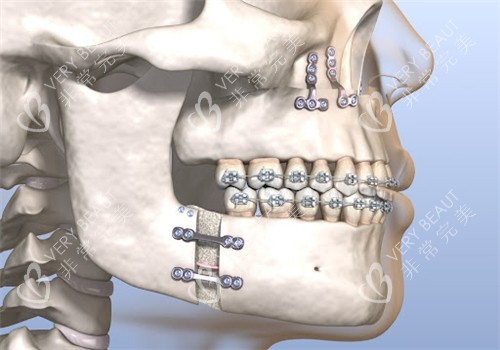

正颌手术是一种复杂的医疗美容手术,旨在通过调整颌骨的位置和形态,改善面部轮廓和咬合功能。

此外,医院还引进了3D头颅数字化技术,能够在手术前对患者的头颅进行三维重建,实现手术过程的可视化,提高手术的精细度和可靠性。

与传统的正颌手术相比,重庆松山整形医院采用的技术能够缩短手术时间周期,患者无需经过长时间的术前正畸咬合调整,可直接进行手术。

此外,医院还引进了数字化微创种植及数字化种植牙修复技术,以及数字化正颌正畸技术,这些技术的应用极大地提高了手术的精度和舒适度。